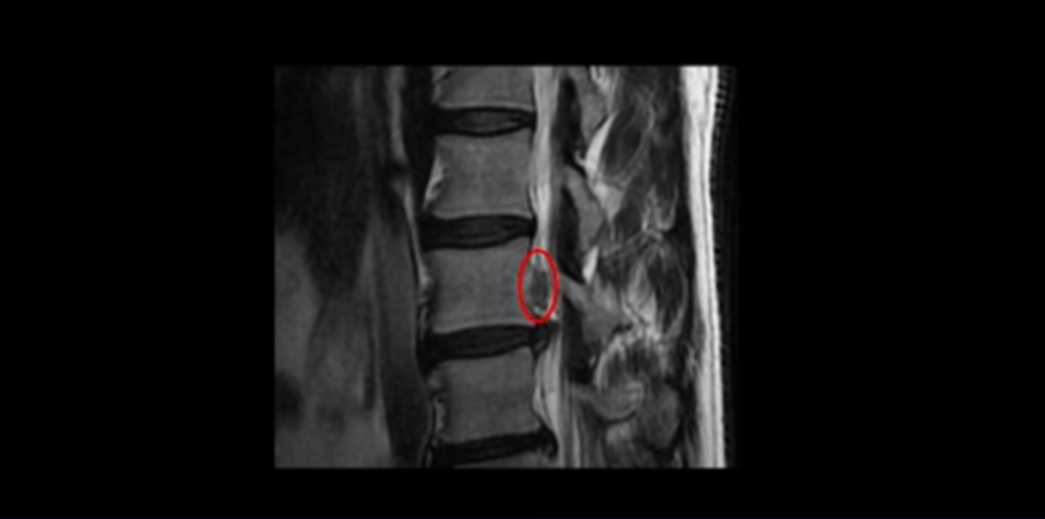

이 환자분 말씀 잘 들으셨습니까? 이분 MRI를 보면 3번과 4번 디스크가 심하게 파열되어 밀려나온 수핵이 위로 밀려 올라가 있습니다. 수핵이 위로 밀려 올라가면서 디스크 본체와의 연결이 끊어져 있습니다.

일반적으로 이런 형태의 밀려나온 수핵이 끊어진 디스크 파열이 훨씬 더 흡수가 잘 됩니다. 그 이유는 뒤에 설명해드리겠습니다.

이분은 오른쪽 허리부터 엉덩이와 허벅지 및 발까지 방사통이 극심하고 감각기능도 떨어졌는데요. 보시다시피 오른쪽 신경 나가는 구멍이 밀려나온 디스크 수핵 때문에 좁아져서 어둡게 보입니다.